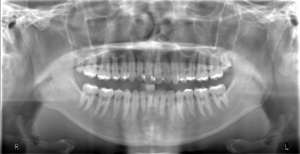

使用装置:モリタ社製ベラビューX800

2021年7月に歯科口腔外科系の撮影を行うパントモCT装置が新たに導入されました。

この装置では、2次元的に歯や顎の撮影を行うオルソパントモ撮影や顎関節撮影に加え、3次元で立体的に歯や病変を描出できるコーンビームCT撮影の機能も搭載されました。そのため従来の装置と比較して、より画質の良い、診断に有用な優れた画像検査が可能となります。

| オルソパントモ画像 | 顎関節断層画像 |